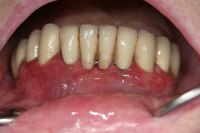

En volymökning av mjukvävnaden kring tänderna som är associerad med intag av läkemedel tillhörande grupperna antiepileptika, immunosuppressiva läkemedel och kalciumblockerare.

Inflammation är den utlösande faktorn som driver tillväxten av mjukvävnaden därför är plackkontroll av största vikt.

Förekomst av gingivala hyperplasier med djupa tandköttsfickor och svåra hygienförhållanden som följd.